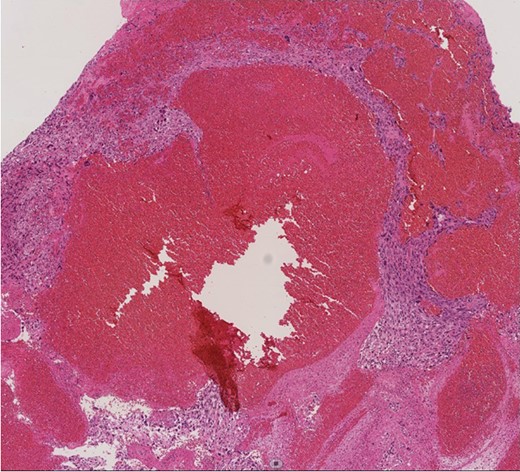

A 60-year-old man presenting with acute onset dyspnea and chest pain was referred to our institution. He had no past medical history. Physical examination was essentially normal except for weak respiratory sounds on the right side. Oxygen saturation was 88%. D-dimer was 1.43 mg/l. The electrocardiogram showed no ST changes. Chest radiography showed an abnormal shadow in the hilum of the right lung. Color Doppler ultrasound showed no deep vein thrombosis. Both the Wells Score and the Revised Geneva Score were 0. Transthoracic echocardiography showed normal left ventricular function (ejection fraction 62%), and no findings of pulmonary hypertension. Contrast-enhanced computed tomography (CT) showed a contrast defect lesion in the right and main pulmonary arteries, as well as a right pleural effusion (Fig. 1). He was initially diagnosed with PE according to the imaging findings and clinical presentation. Anticoagulant therapy (intravenous heparin infusion) was then started. Follow-up CT showed a larger defect lesion in the pulmonary artery, and the decision was then made to proceed with urgent pulmonary embolectomy because it was refractory to anticoagulant therapy. Cardiopulmonary bypass was established with aortic and bicaval cannulation. Deep hypothermic circulatory arrest was used every 10 minutes to obtain a bloodless field during pulmonary embolectomy. The right pulmonary artery was incised, and it was filled with a red, solid mass (Fig. 2). The mass was resected, and the pathological diagnosis during surgery was PAS. Because of the urgent situation, only endarterectomy, not pneumonectomy for radical resection of the tumor, was performed. On postoperative Day 7, CT showed residual lesions in the right pulmonary artery. The pathology report showed high-grade undifferentiated PAS (Fig. 3). The patient refused radical tumor resection by pneumonectomy, as well as postoperative radiation and chemotherapy. He died 5 months after the surgery.

Extensive contrast-deficient images ae present from the pulmonary artery trunk to the right pulmonary artery.